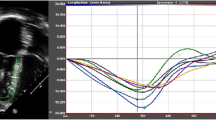

Velocity-encoded flow measurements

Flow velocity-encoded MR imaging data were analysed by two readers (A.H. and K.B.) in consensus by using the same analytical software package as mentioned above (ARGUS, Siemens Medical Solutions, Erlangen, Germany). Within the mitral and tricuspid valve areas of maximum flow velocity were assigned on a visual basis on every slice (Fig. 4) and a region of interest (ROI) of 1 cm2 was centrally positioned in this area. Flow curves were obtained by automatic measurement of peak flow velocity within these areas. MR imaging-derived recording of diastolic ventricular inflow has, similar to echo-Doppler images, a characteristic biphasic appearance (Fig. 3). Two distinct peaks represent early and late diastolic ventricular filling.

Diastolic function parameters derived from the inflow curves were as follows: peak flow velocity during early diastolic filling, represented by the amplitude of the e-wave, peak flow velocity during late diastolic filling by atrial contraction, represented by the amplitude of the a-wave. Hereafter ratios of peak velocity of the e-waves and peak velocity of the a-waves (e- to a-wave ratios) were calculated for the tricuspid and mitral valves. The results of patients with CP were compared with those of healthy volunteers. Additionally, the subgroup of patients with only minor pericardial thickening was compared with patients with pericardial thickening of more than 4 mm. Furthermore, the correlation coefficient of transtricuspid e- to a-wave ratios with right ventricular end-diastolic pressure measurements was assessed and intra-individual correlation coefficients of the mitral and tricuspid e- to a-wave ratios were calculated (Fig. 5).

The evaluation of correlation between the right ventricular e- to a-wave ratios and right ventricular end-diastolic pressure measurements of the intracardiac catheter examinations resulted in a correlation coefficient of r = 0.6 (p = 0.01; Fig. 6).

The assessment of intra-individual correlation of e- to a-wave ratios of the measurements across the mitral and the tricuspid valves revealed a good correlation in the healthy subjects (r = 0.86; p < 0.0001). The e- to a-wave ratios of mitral and tricuspid valves showed no significant correlation in patients with CP (r = −0.04; p = 0.86)

Constrictive pericarditis predominantly presents with signs and symptoms of diastolic right heart failure. The aim of this study was therefore in particular to evaluate right ventricular diastolic function in patients with constrictive pericarditis by using velocity-encoded flow measurements at the level of the atrioventricular valves. The major important findings were: (a) The e- to a-wave ratios measured at the tricuspid valves correlated with intracardiac right ventricular catheter measurements in patients with CP. (b) While left and right ventricular e- to a-wave ratios showed a good correlation in healthy subjects, none was present in CP. (c) Abnormal septal movement was seen in all patients but one.

However, a comprehensive MR examination with evaluation of pericardial thickness, right end-diastolic volumes and the evaluation of septal motion during diastole can contribute information to identify patients with CP with a high sensitivity and specificity. As shown in Table 4 and as previously published by Giorgi et al. [19], abnormal septal motion allows one to discriminate CP patients from healthy subjects and patients with restrictive cardiomyopathy with a high diagnostic accuracy. The predominantly right-sided intracardiac pressure elevation in CP, which contributes to this phenomenon, is typically measured in intracardiac catheter examination. The calculation of the correlation coefficients of right ventricular pressures and e- to a-wave ratios in our patients with CP resulted in a value of r = 0.6 (p = 0.01; Fig. 6). Similar observations have been made for the left ventricle in echocardiography in several disease entities, but to our knowledge no data exist for right ventricular measurements so far [33, 34].

Further diagnostic information may be obtained by a correlation of the intra-individual tricuspid and mitral e- to a-wave ratios. In healthy populations, close correlations have been found between individual right and left ventricular diastolic parameters [35, 36]. Constrictive pericarditis predominantly involves right ventricular diastolic function to a variable extent, independent from an involvement of the left ventricular diastolic function—which may, however, appear in the course of the disease. Therefore this close correlation is lost in CP (Fig. 5).